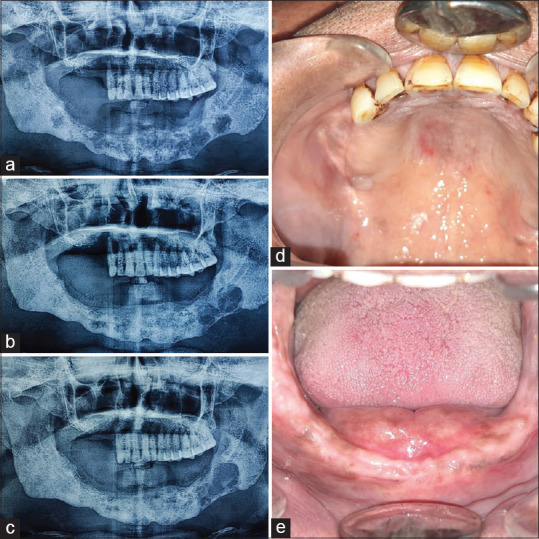

Patient concerns and diagnosis: A 48-year-old male presented with swelling and tooth mobility since 6 months. Orthopantomogram revealed extensive destruction in the mandible and right maxillary posterior region. Histological examination confirmed LCH using immunohistochemical staining with S-100, CD1a.

Outcome: Three months post-treatment, remission was observed, though some residual lesion remained. Follow-up at six months showed no further disease progression, supporting the efficacy of corticosteroid injections.